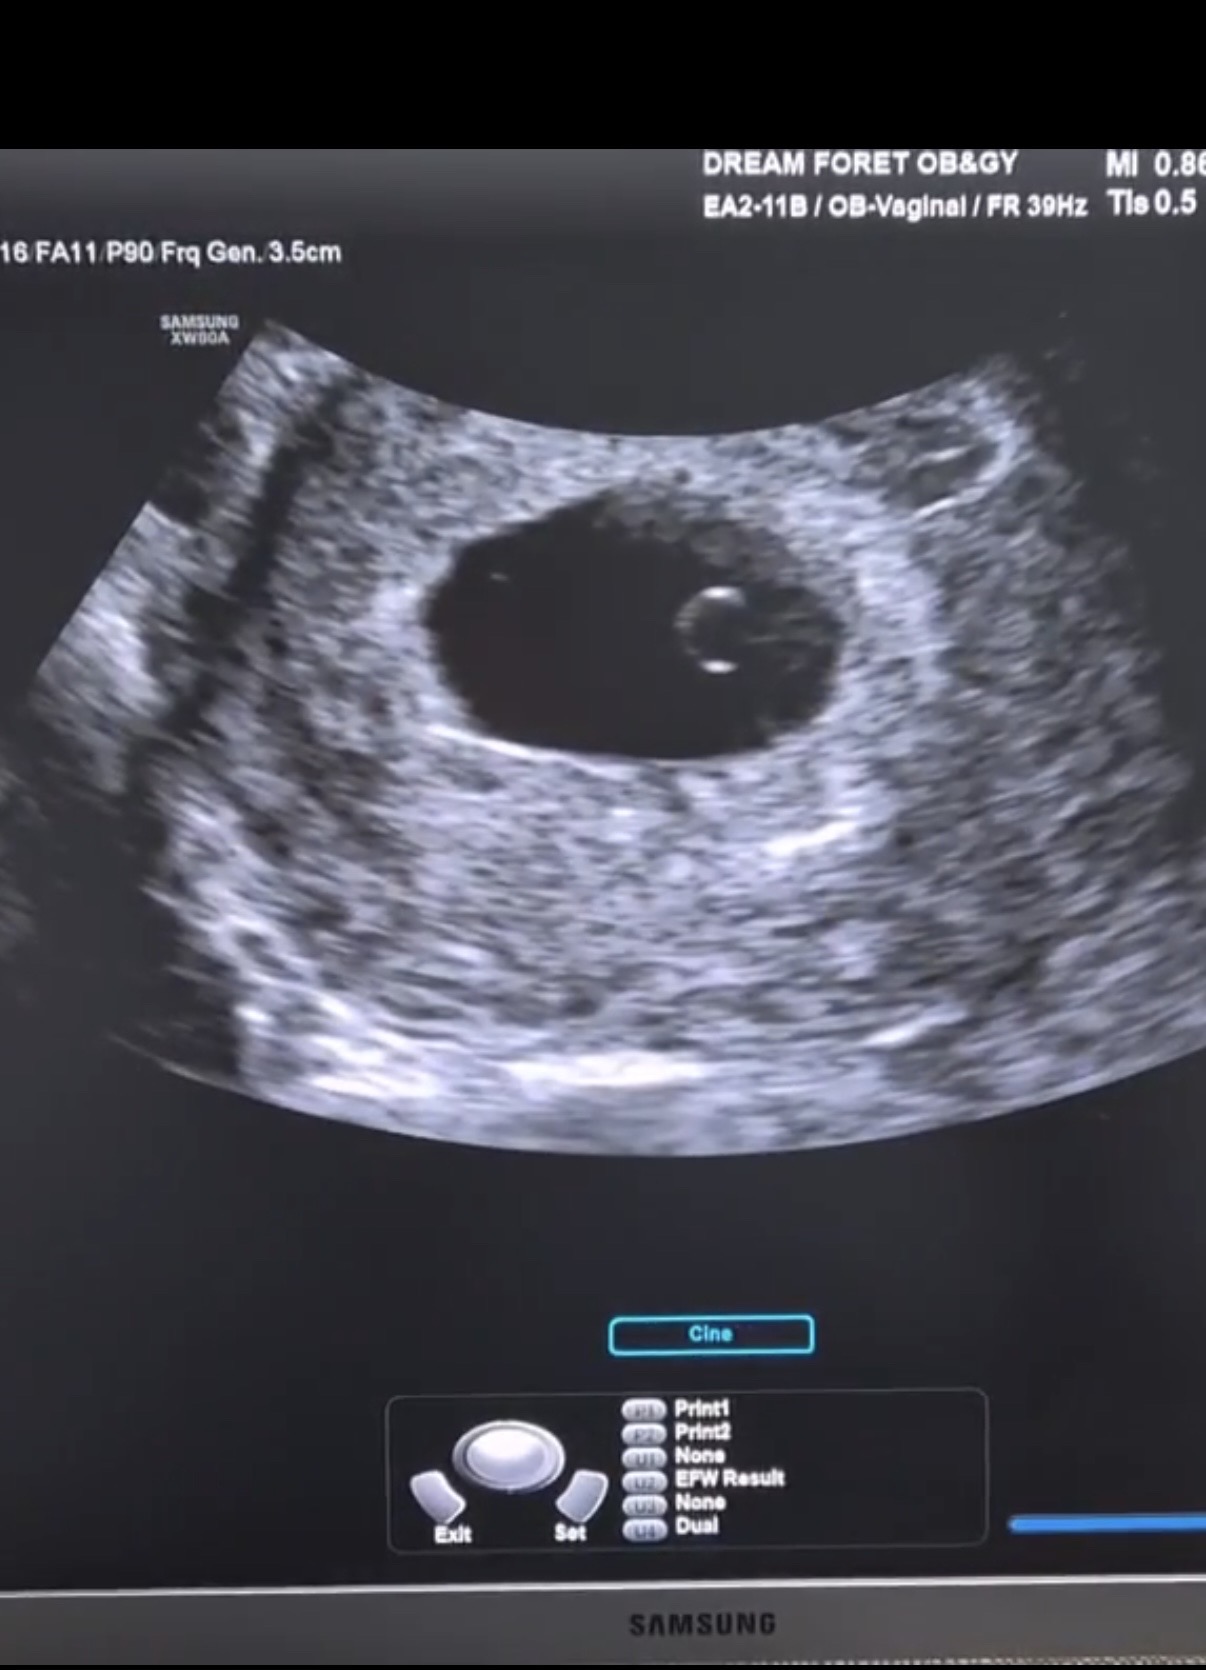

5주차 난황 확인했어요𖤐

주말에 병원 가서 아기집이랑 난황 보고 왔어요!! 막생 기준 5주 6일이었는데, 병원에서는 5주 1일차라고 하시구 예정일 얘기해주셨어요 ㅎㅎ 일주일 전에는 안보이던 아기집이랑 난황이 보여서 신기했어요☺️ 이제 심소 들으면 더 신기하겠죠?👶🏻